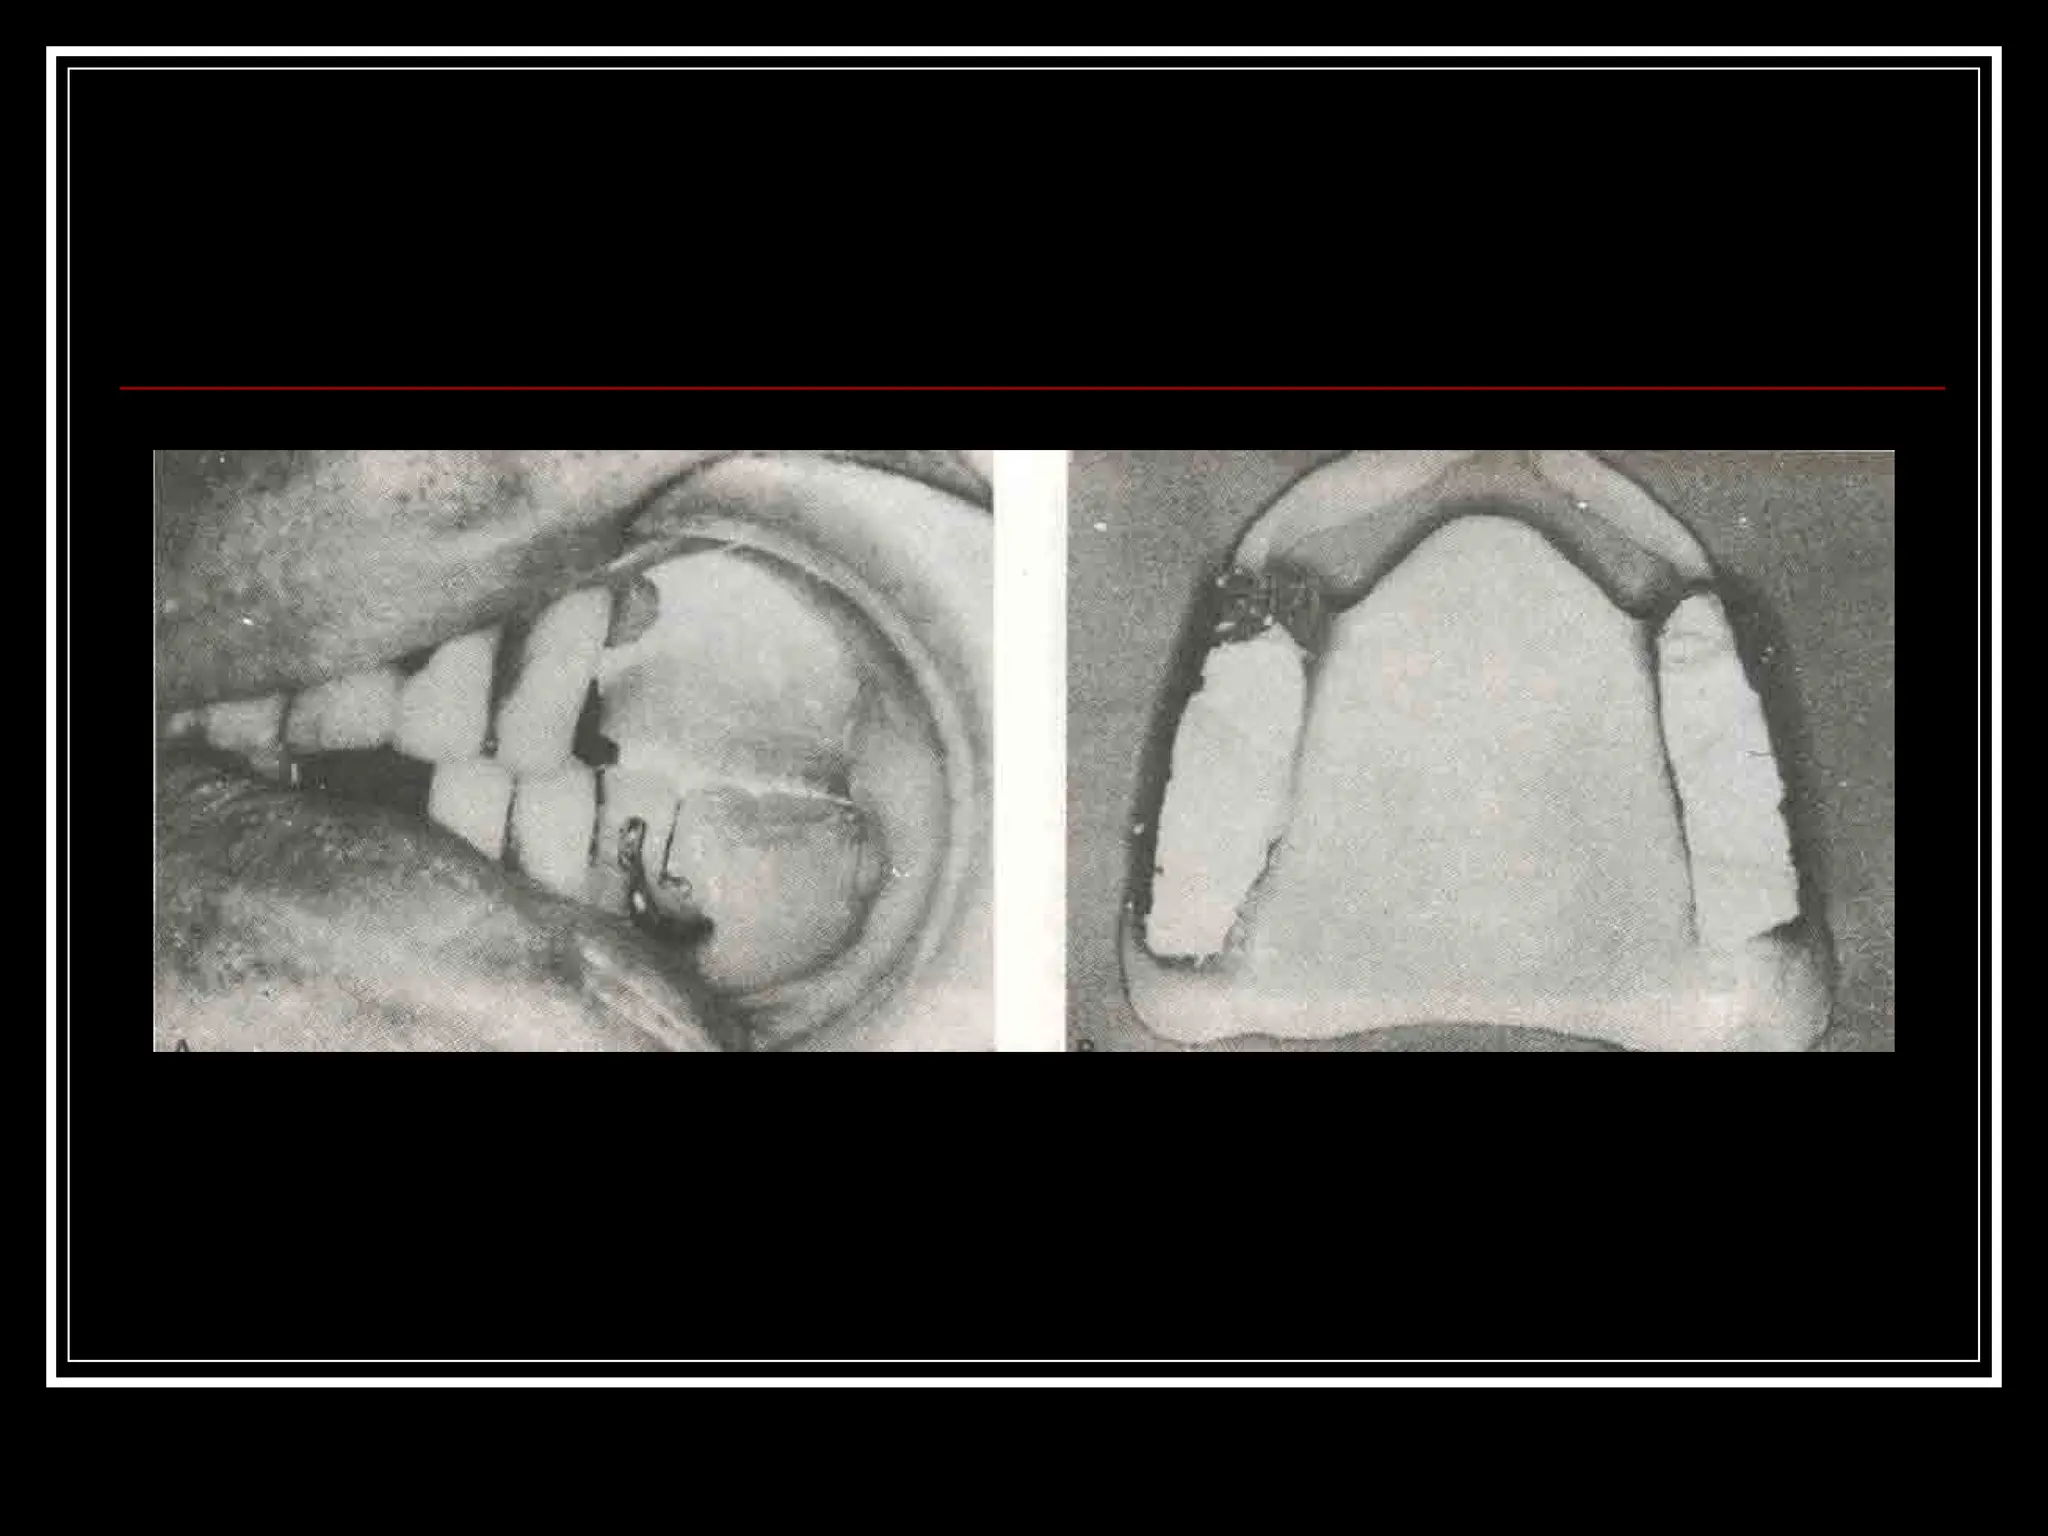

Ashok Soni etal (2000)  Trial anterior artificial tooth arrangement for an immediate denture patient :A clinical report  A technique is described that allows the esthetic try-in of the maxillary anterior artificial tooth before the extraction and completion of an immediate denture

Intra oral view Posterior artificial tooth try in done with modified anterior wax up in anterior labial flange area.

Try in ofposterior artificial tooth arrangement with processed maxillary denture.

 To relatethe maxillary denture to remaining teeth and supporting tissues, an impression of the adjusted denture was made and a new maxillary cast fabricated.

 The maxillary artificialanterior teeth were arranged to reflect the position of the patients natural teeth.

 Labial indexof the completed anterior artificial tooth arrangement was made with impression plaster.

 After theseparation of the index the teeth were fixed using autopolymerizing acrylic resin.  Denture was finished and inserted immediately after the extraction.